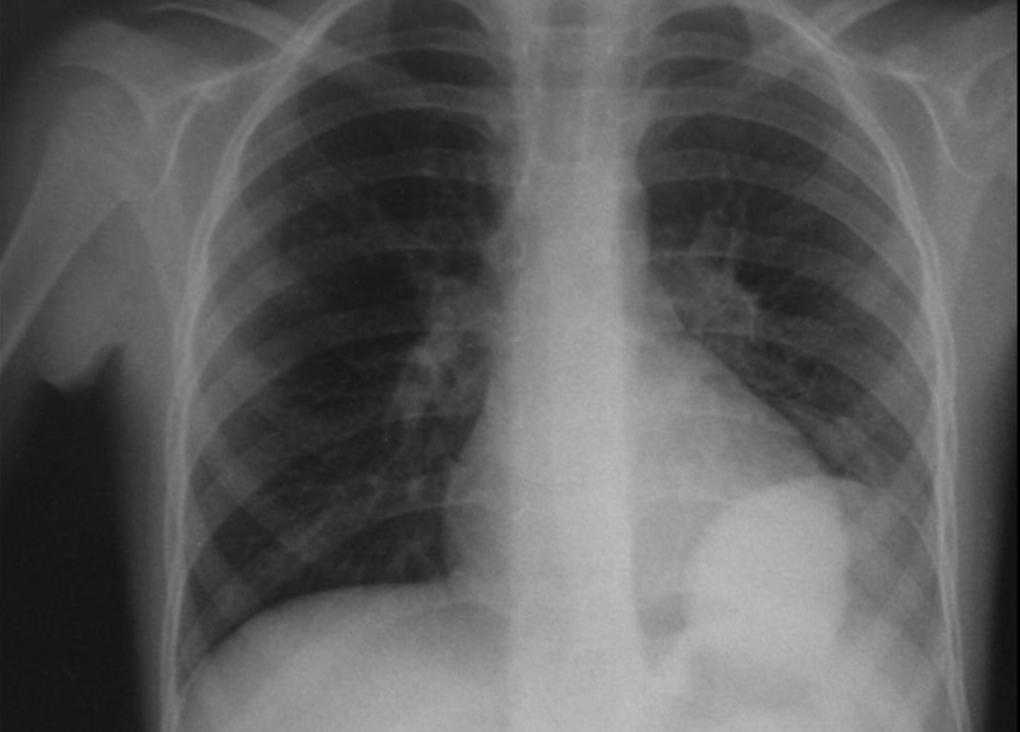

Изучение дозы излучения при рентгеновских исследованиях: визуализация